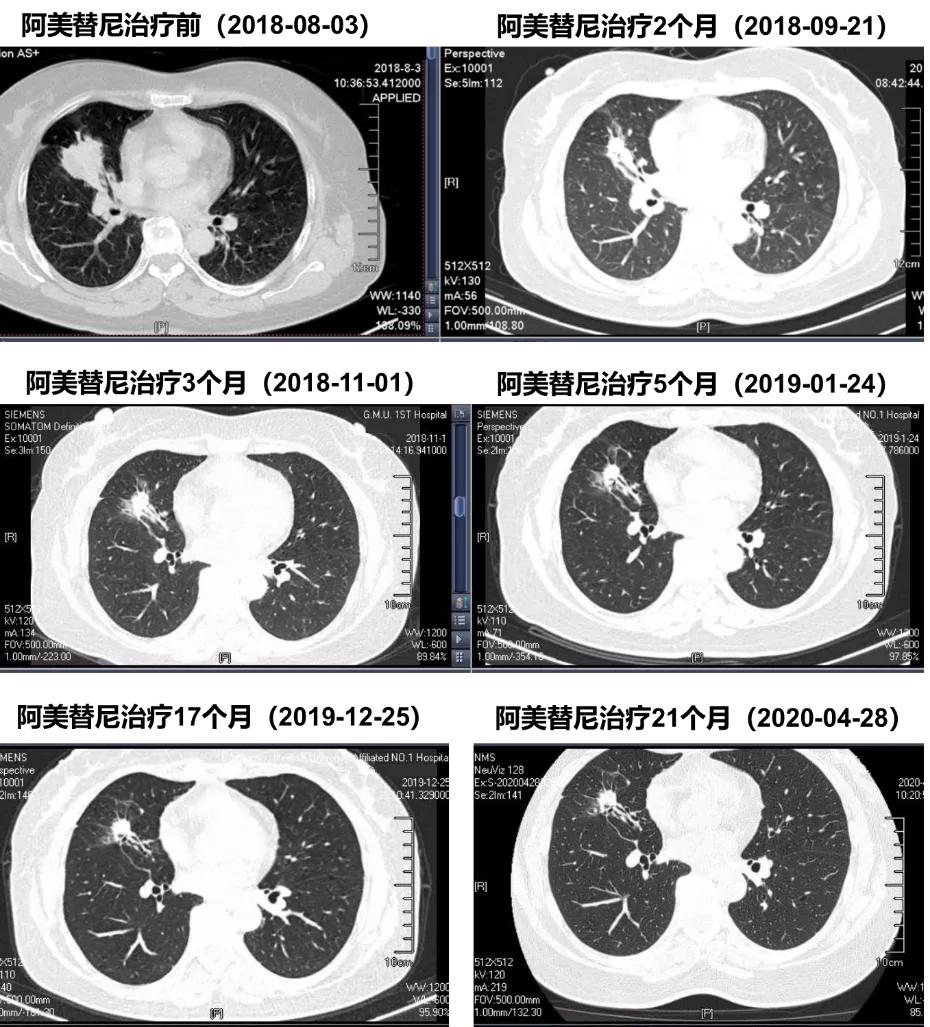

阿美替尼二线治疗患者CT随访

胸部CT显示:阿美替尼治疗1个月后,疗效达到PR,且后续治疗过程中,病灶持续好转。